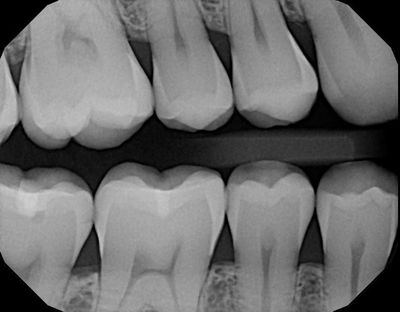

There are two types of dental x-rays you will come across: 1) Full mouth series/bitewings/periapicals, and 2) Panelipse (pano). Let's quickly breakdown the two and what the differences are.

During your initial visit your dental team will take a full mouth series of x-rays. This is a set of 18 x-rays (14 periapical's and 4 bitewings). This set of x-rays is completed only once every 3 to 5 years depending on your periodontal status. This full mouth set of x-rays will take individual radiographs (periapicals, or "PA's") of each tooth. The dentist is looking at your bone levels, sinsuses, infections and any abnormalities of the tooth and/or root structure. Changes in teeth usually are slow or chronic, this is why you take these x-rays less frequently, unless you have an emergency. In addition, 4 bitewing x-rays (see picture above), these are your cavity detecting x-rays. Changes in the density of your tooth enamel will show the dentist where cavities are.

You can expect an annual set of bitewings. Bitewings are very useful to catch dental caries ("cavities") early before they reach to far into your tooth.